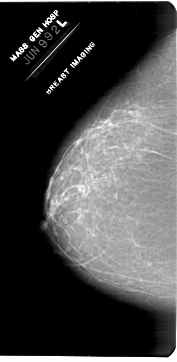

ics_version 1.0 filename A-1953-1 DATE_OF_STUDY 9 6 1992 PATIENT_AGE 50 FILM FILM_TYPE REGULAR DENSITY 2 DATE_DIGITIZED 4 3 1999 DIGITIZER HOWTEK 43.5 SEQUENCE LEFT_CC LINES 6871 PIXELS_PER_LINE 3361 BITS_PER_PIXEL 12 RESOLUTION 43.5 NON_OVERLAY LEFT_MLO LINES 6871 PIXELS_PER_LINE 3526 BITS_PER_PIXEL 12 RESOLUTION 43.5 NON_OVERLAY RIGHT_CC LINES 6616 PIXELS_PER_LINE 3436 BITS_PER_PIXEL 12 RESOLUTION 43.5 OVERLAY RIGHT_MLO LINES 6871 PIXELS_PER_LINE 3631 BITS_PER_PIXEL 12 RESOLUTION 43.5 OVERLAY |